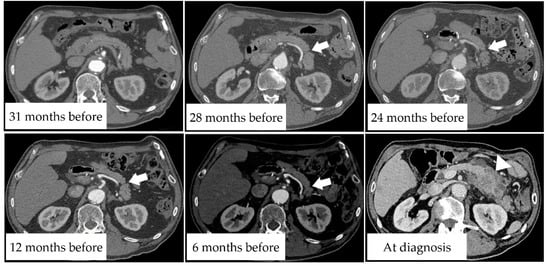

3.5. Case Presentation